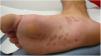

A 26-year-old man with no relevant history was seen at the emergency department for asymptomatic palmoplantar lesions that had appeared 3 weeks earlier and had not responded to topical prednicarbate treatment (twice daily for 20 days). The patient reported no fever or systemic symptoms. He had no history of oral or genital ulcers in the preceding weeks or months, and reported no risky sexual relations. Physical examination revealed erythematous oval plaques, some of which showed fine collarette scaling, located on the palms (Fig. 1), soles, and lateral aspects of the feet (Fig. 2). Histology showed superficial lymphocytic perivascular dermatitis with minimal epidermal exocytosis associated with mild spongiosis (Fig. 3). Immunohistochemistry for Treponema pallidum was negative. Serological screening using chemiluminescence immunoassay to detect total antibodies against T pallidum was initially negative. Screening was repeated 1 month later, together with visually interpreted treponemal and non-treponemal tests (T pallidum hemagglutination assay [TPHA] and rapid plasma reagin [RPR] tests), all of which were negative. The lesions resolved without treatment after 4 weeks, and the patient remained free of lesions during follow-up, which ended when he again tested negative in a T pallidum screening test 3 months after lesion resolution. Based on the clinical course and the clinical, histological, and laboratory data, a diagnosis of atypical palmoplantar pityriasis rosea (PR) was established.